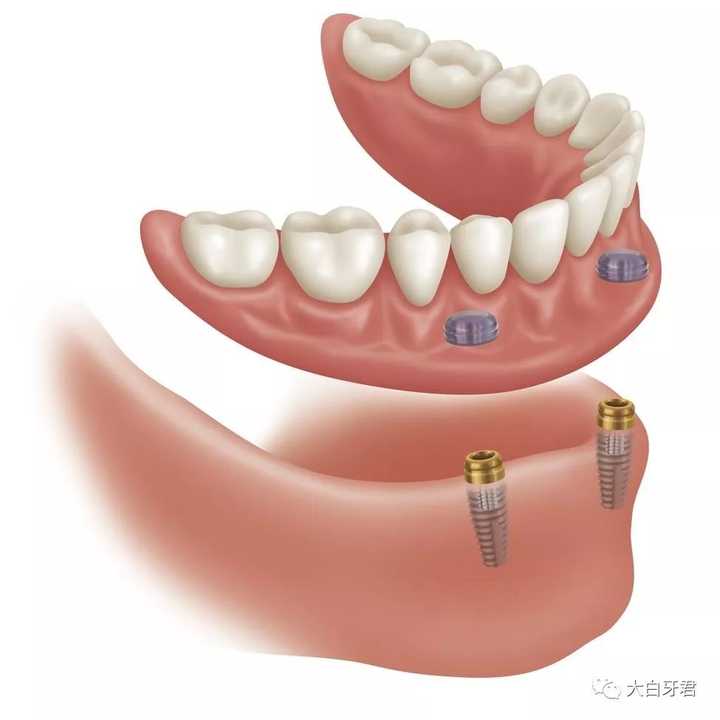

又比如全口牙缺失,除了做全口的活动假牙外,还可以利用种植牙的技术,或再增加几个磁铁来增加全口假牙的稳定性,曾经大家看到的「笑掉假牙」的情况就可以避免咯!

活动假牙也可以和种植牙相配合,更加稳固